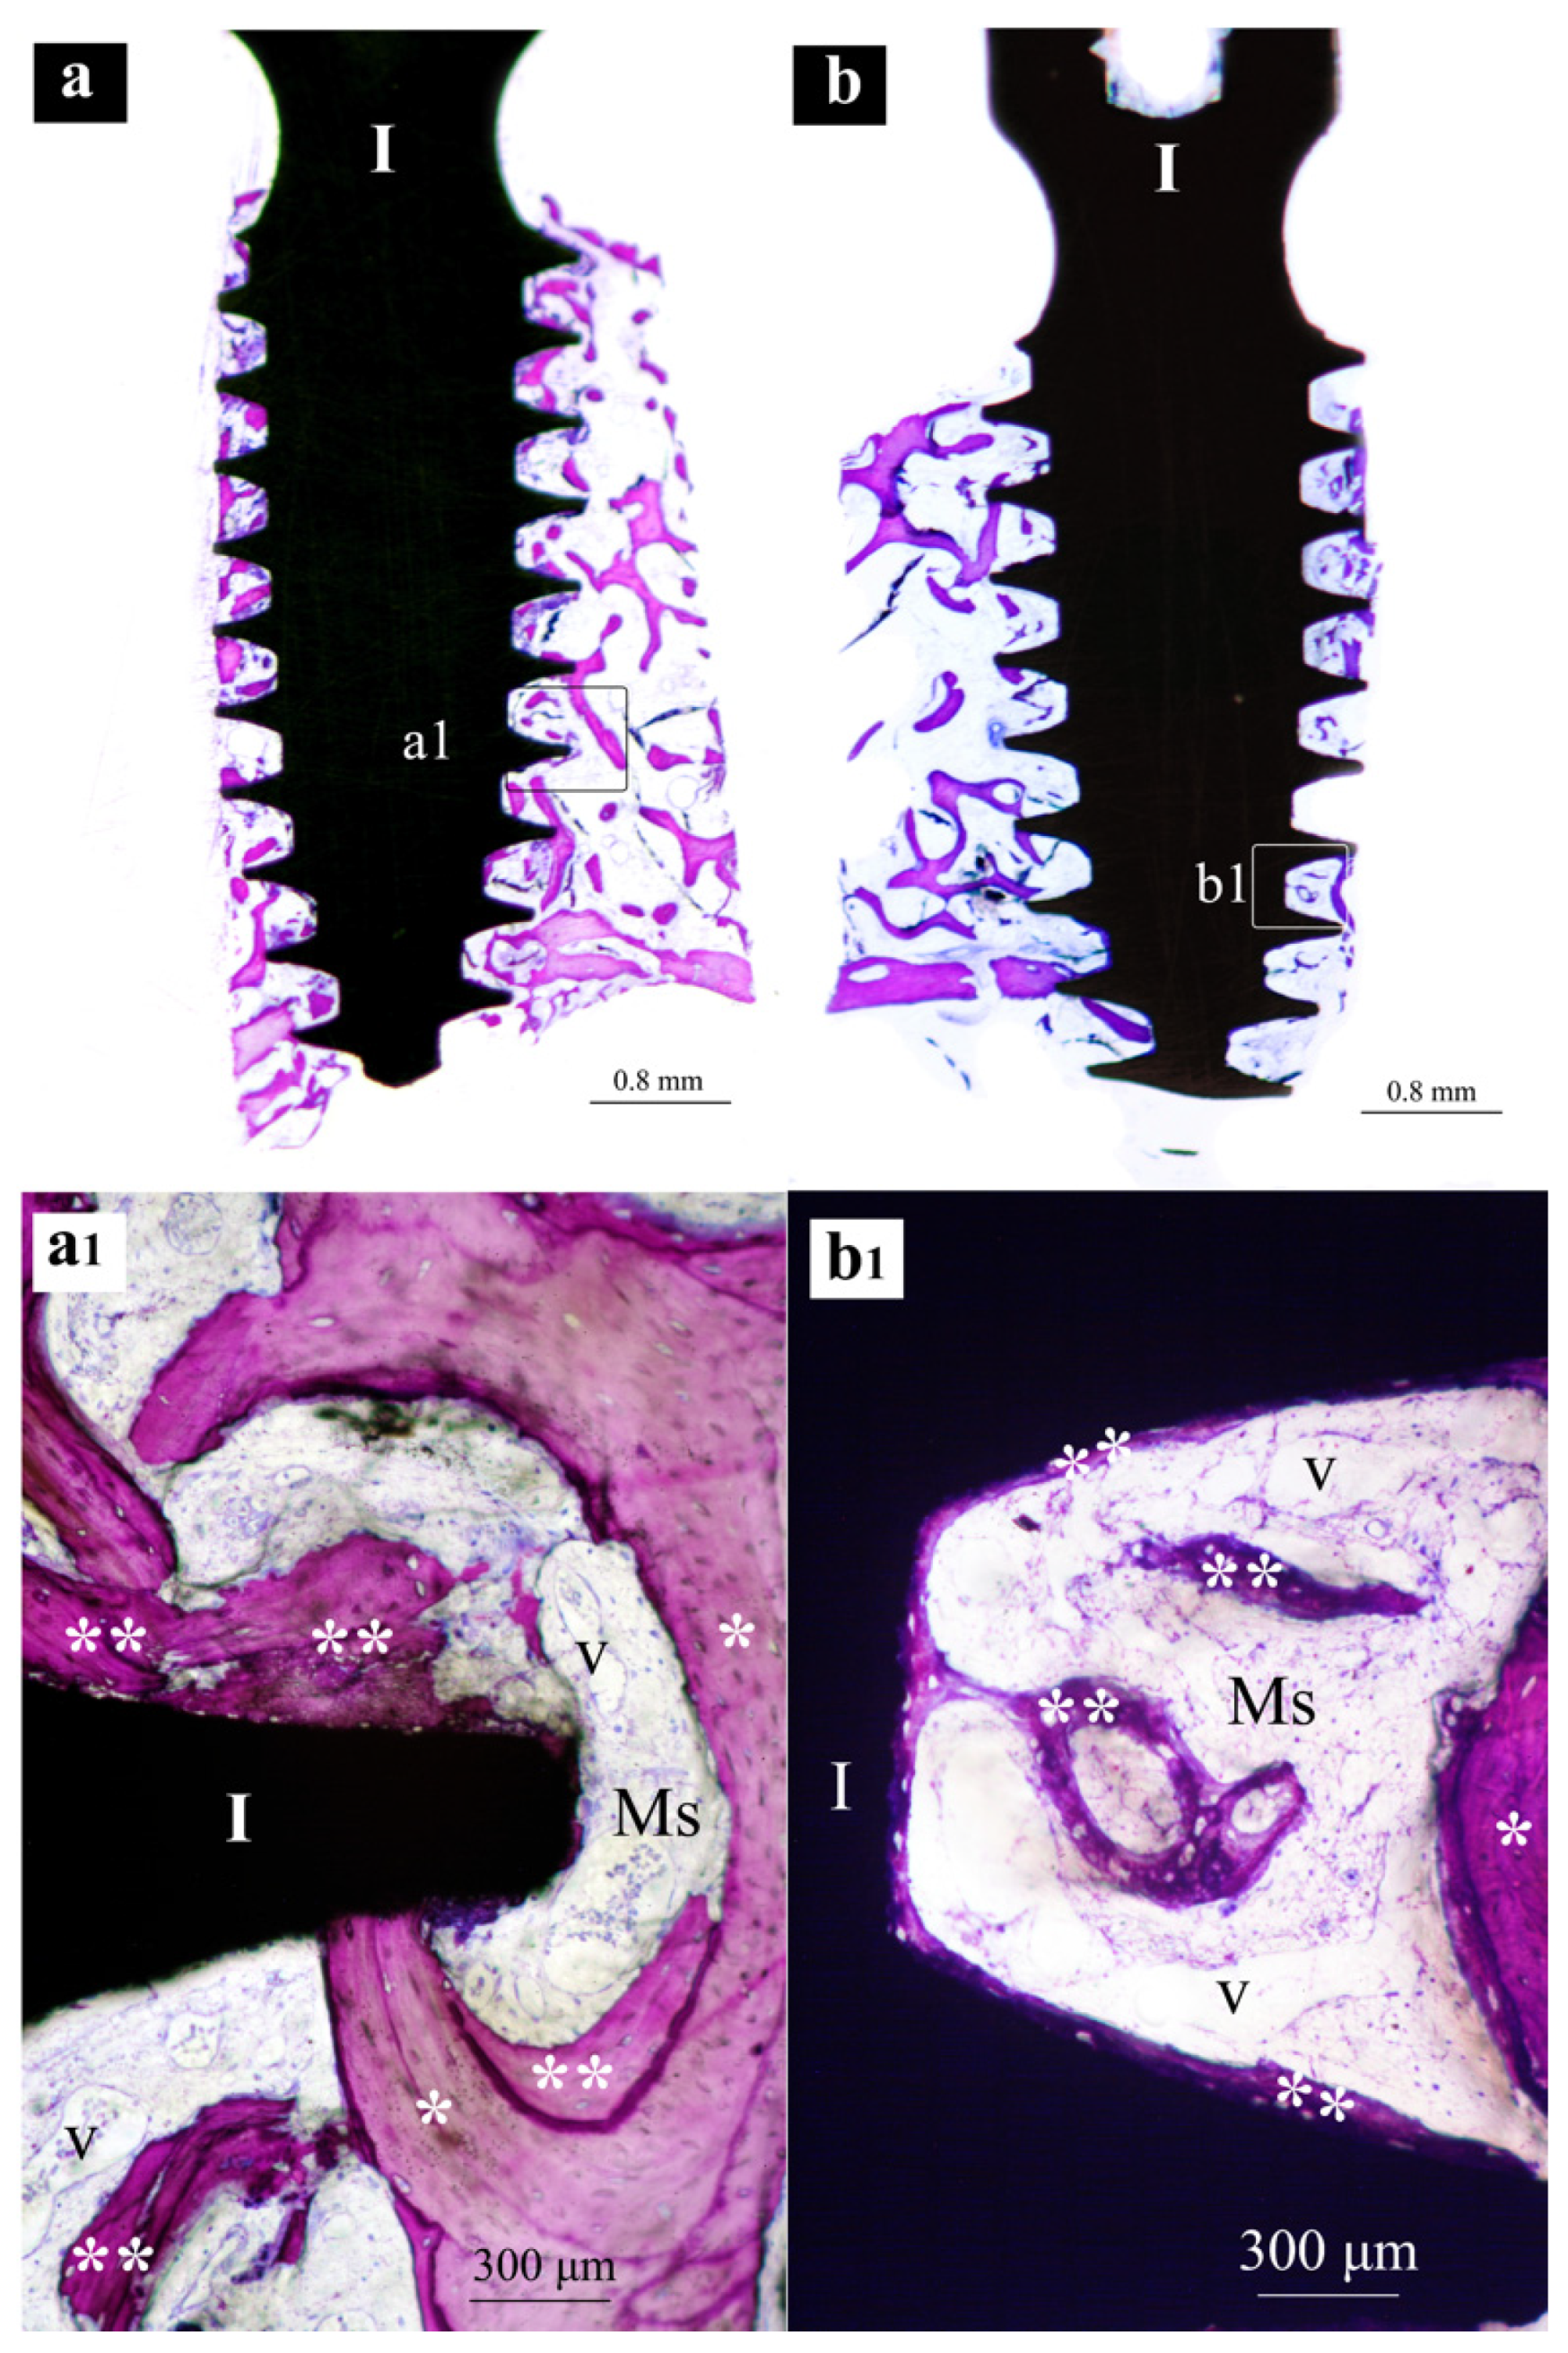

3.1. Histological

- Both SLA and XPEED® surfaces showed bone formation with direct-contact osteogenesis.